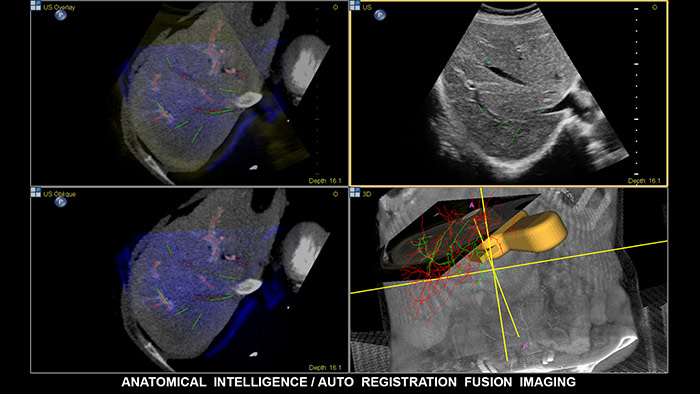

Fusión de imágenes y navegación

La fusión de imágenes combina las ventajas inherentes de la adquisición de imágenes de multimodalidad directamente en el sistema de ultrasonidos mediante seguimiento electromagnético. Al combinar TC/RM/PET con ultrasonidos en tiempo real y la posición en tiempo real del paciente, el profesional sanitario cuenta con una potente herramienta de diagnóstico y, al mismo tiempo, limita la radiación debido a que se necesitan menos exploraciones de confirmación; de este modo, se potencia la productividad del departamento. EPIQ, con su exclusivo sistema de ultrasonidos con inteligencia anatómica (AIUS), ofrece fusión de imágenes con registro automático de volúmenes de TC/RM y ultrasonidos, tarea para la que se emplea una décima parte del tiempo que suele durar la alineación. La navegación guiada por aguja es una herramienta que mejora el rendimiento en las intervenciones hepáticas más complejas; además, se ha demostrado que mejora el flujo de trabajo y reduce la exposición a la radiación al necesitarse menos exploraciones de confirmación. EPIQ de Philips incluye una gama completa de soluciones, entre las que cabe destacar las siguientes: CIVCO eTrax™, el localizador de aguja adaptativo de Philips y los localizadores de aguja coaxial de Philips. De esta manera, el profesional sanitario, al disponer de una compatibilidad tan amplia con los dispositivos de biopsia y ablación, es libre de elegir las mejores herramientas para el procedimiento en función del grado de complejidad.

Fusión y navegación

Tome decisiones con seguridad incluso en casos diagnósticos complicados con ayuda de las funciones de fusión de imágenes y navegación guiada por imagen de Philips. El flujo de trabajo agilizado permite que los profesionales sanitarios consigan una fusión eficaz de TC/RM/PET con ultrasonidos en tiempo real; a su vez, la navegación guiada por aguja ayuda a guiar la biopsia de lesiones pequeñas y de difícil acceso.